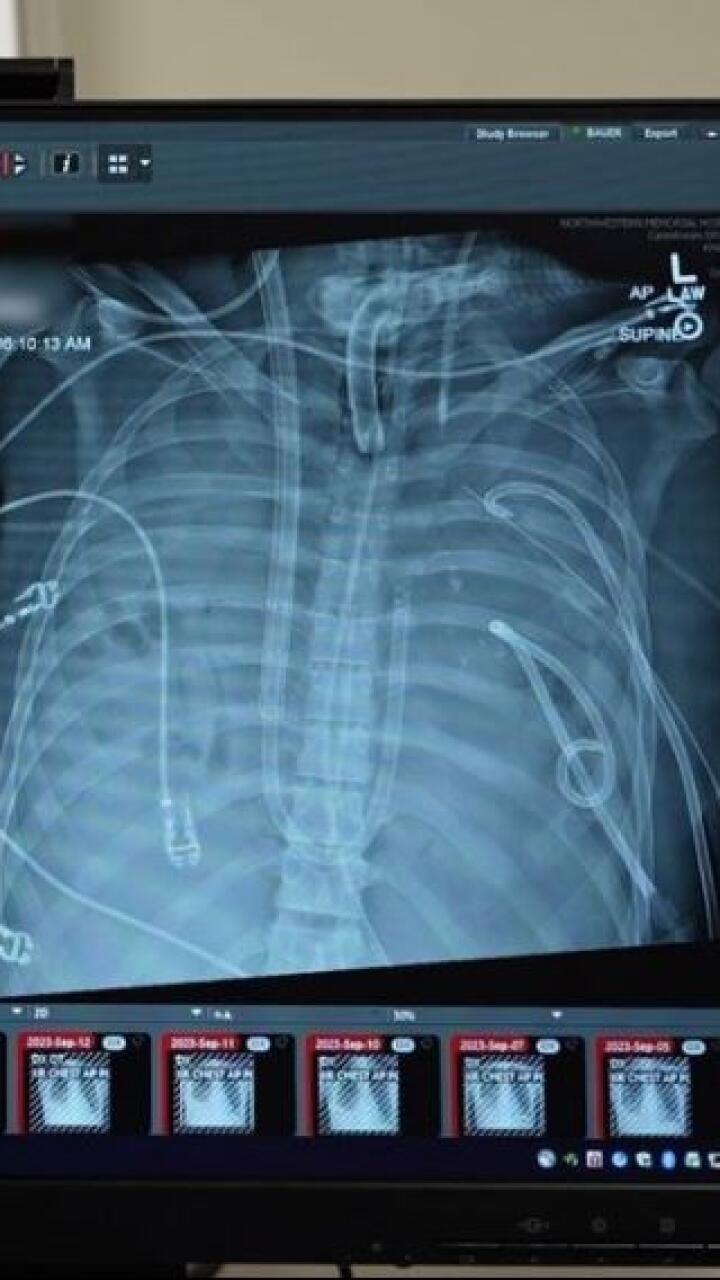

Hombre perdió ambos pulmones por usar vapeadores y gracias a implantes mamarios logró seguir con vida

Davey Bauer, de 34 años, utilizó vapeadores durante casi una década y sus pulmones sufrieron las consecuencias.

No solo consumía vapeadores, también fumaba cigarrillos, lo cual le causó una grave infección pulmonar tras contraer gripa. Los médicos le informaron que perdería ambos pulmones y que necesitaría un trasplante.

Era una cirugía peligrosa, pues al momento de quitar los órganos, Davey podía morir de inmediato.

Según el medio NBC, los médicos indujeron a un coma a Davey para conectarlo a un ventilador que le ayudara a respirar.

Debido a que su condición seguía deteriorándose, fue trasladado al Northwestern Medicine en Chicago, Estados Unidos, para someterlo a una cirugía de emergencia.

Para evitar que su corazón se moviera o cayera al fondo de la caja torácica, los cirujanos optaron por colocarle un par de implantes mamarios DD en el espacio donde estaban los órganos.

“Una vez que extirpamos los pulmones, nos dimos cuenta de que ahora teníamos que apoyar el corazón. Estábamos buscando lo más grande que pudiera caber en su cavidad torácica”, explicó el cirujano Ankit Bharat.

Los médicos aseguraron que era la primera vez que se utilizaban implantes mamarios en un trasplante doble de pulmón.

Gracias a que los implantes lograron mantener el corazón de Davey en su lugar, los médicos pudieron eliminar la infección.

Dos días después del procedimiento, le fueron retirados los objetos y trasplantaron con éxito los pulmones.